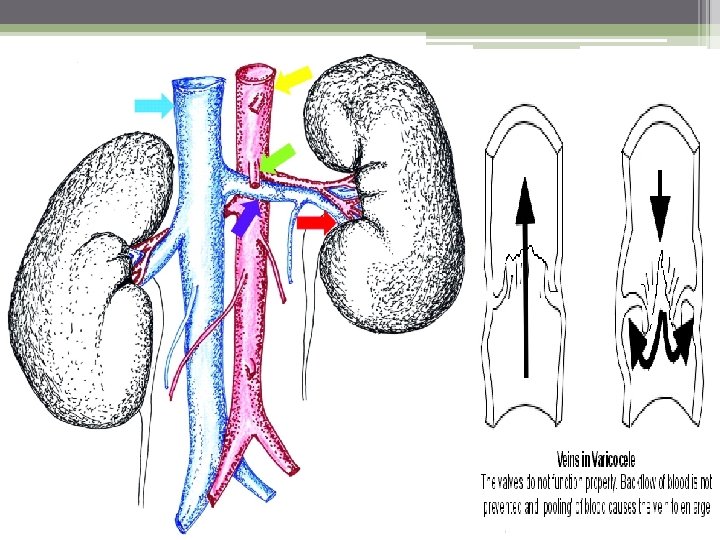

Etiology Varicoceles are much more common (approximately 80 -90%) in the left testicle than in the right because of several anatomic factors, including: 1) the angle at which the left testicular vein enters the left renal vein. 2) the lack of effective antireflux valves at the juncture of the testicular vein and renal vein. 3) the increased renal vein pressure due to its compression between the superior mesenteric artery and the aorta( the nutcracker phenomenon) 4) Increased length of the left testicular vein: The left vein is 8 -10 cm longer than the right testicular vein

80% of men with a left clinical varicocele had bilateral varicoceles revealed by noninvasive radiologic testing. Lt. spermatic vein pressure=10 mm Hg and ends in lt. renal vein which pressure =10 mm. Hg. so any strain can be detected by increase intra abdominal pressure by valsalva m. In Rt. side : Rt. spermatic vein pressure =10 mm Hg and ends in IVC which pressure =ZERO. So due to increase intra abdominal pressure not increasing pressure Over Rt. spermatic vein. Right side varicocele : We shoud consider possible retroperitoneal pathology (eg, renal cell carcinoma) As the cause of spermayic vein compression. Investigate further with approprite ultrasonography Or Ct scanning befor repairing the varicocele.